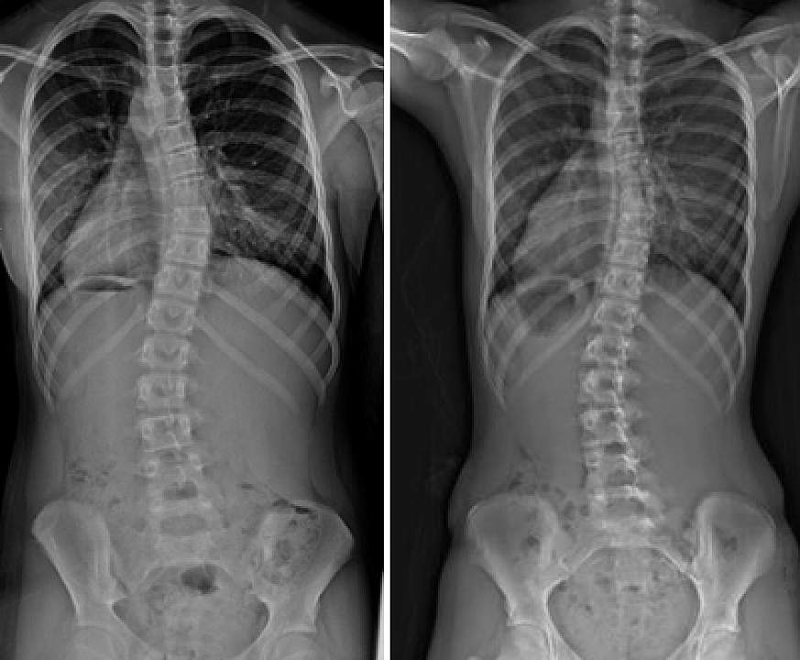

Một số thanh thiếu niên bị vẹo cột sống nặng cần một loại phẫu thuật gọi là hợp nhất cột sống. Trong quá trình phẫu thuật, bác sĩ phẫu thuật chỉnh hình sẽ làm thẳng cột sống càng nhiều càng tốt và giữ nó cố định bằng thanh và ốc vít. Bằng cách đó, đường cong sẽ được cải thiện. Sau khoảng một năm, xương sẽ được hợp nhất hoàn toàn. Những thanh kim loại không còn cần thiết nữa, nhưng nó được để lại trong cơ thể vì nó không gây hại gì và việc đưa chúng ra ngoài cần phải thực hiện một cuộc phẫu thuật khác.

Chứng vẹo cột sống ở thanh thiếu niên thường là vô căn và xảy ra trong thời kỳ tăng trưởng cao nhất của trẻ từ 13 đến 15 tuổi. Độ cong phát triển vào thời điểm đó có thể ảnh hưởng không chỉ đến chức năng cột sống của cá nhân mà còn cả sự tự tin của họ. Việc nắn thẳng những chiếc đốt sống bị lệch nặng sẽ loại bỏ nỗi lo lắng đó để những người trẻ tuổi có thể tập trung vào mọi thứ khác đang diễn ra trong cuộc sống.